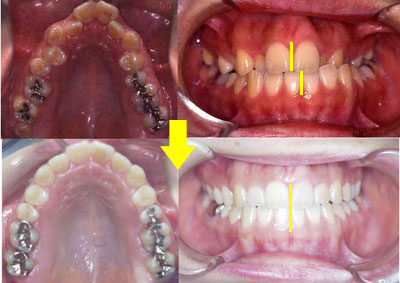

下顎は受け口、上顎は著しい乱くい歯です。永久歯を4本間引きして治療する事も考えられますが、当医院では永久歯を一本も抜かないで治療しました。

治療前(初診時)9歳

治療後 12歳

治療期間 2年5ヶ月